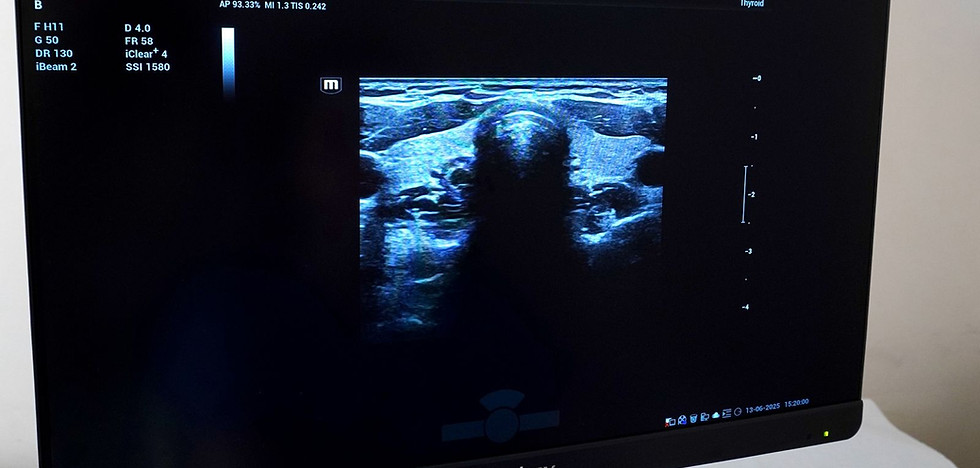

Clinic GI Rimoni has been equipped with a premium-class device, Mindray Resona i9 elite edition.

The device works on the latest zst + platform, which ensures the highest image quality and, accor...

Book your thyroid ultrasound at GI Rimon:

– If you feel tired or irritable– If there is a family history of thyroid disease– If you feel a “lump in the throat”